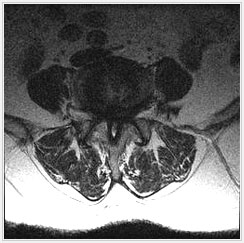

ôÃß°ü ÇùÂøÁõÀ̶õ?

ôÃß°üÀº ô¼ö(³ú±â´É°ú »çÁö, ¸öüÀÇ ±â´ÉÀ» ¿¬°áÇÏ´Â ±¸Á¶¹°)¸¦ º¸È£ÇÏ´Â ±¸Á¶¹°·Î¼­ ³ªÀ̰¡ µé¾î°¨¿¡ µû¶ó ôÃß¿¡¼­ µÎ °¡Áö º¯È­°¡ ¹ß»ýÇÏ°Ô Çϴµ¥ Çϳª´Â °ñ´Ù°øÁõ, ¶Ç ´Ù¸¥ Çϳª´Â ôÃß°ü ÇùÂøÁõÀ¸·Î¼­ ôÃß°ü ÇùÂøÁõÀº ÅðÇ༺ ôÃßÁúȯÀÔ´Ï´Ù.

°¡Àå Æ¯Â¡ÀûÀÎ Áõ»óÀº °£ÇæÀûÀÎ ½Å°æÀμº ÆÄÇàÀ̶ó°í ÇÏ¿© Ãʱ⿡´Â ¿À·¡ °ÉÀ¸¸é ÀåµýÁö°¡ ¾ÆÆÄ¿ÀÁö¸¸ ½ÉÇØÁö¸é ¹ö½ºÁ¤·ùÀå ÇϳªÀÇ °Å¸®µµ °ÈÁö ¸øÇÏ¿© ½¬¾ú´Ù °¡¾ßÇÏ¸ç ¾ÆÁÖ ½ÉÇÑ °æ¿ì´Â ¼­ ÀÖ´Â °Í Á¶Â÷ Èûµé¾îÇÏ°Ô µÇ¾î Á¤»óÀûÀÎ º¸ÇàÀÌ ¾î·Æ°Ô µË´Ï´Ù. ƯÈ÷ Ãß°£ÆÇ Å»ÃâÁõ°ú µ¿¹ÝµÇ´Â °æ¿ì¿¡´Â ´Ù¸®ÂÊÀÇ Àú¸²Áõ»ó°ú ´ç±â´Â Áõ»óÀÌ ´õ¿í ½ÉÇÏ°Ô ³ªÅ¸³ª°Ô µË´Ï´Ù.

* ¼ö¼úÀû Ä¡·á : À§¿Í °°Àº º¸Á¸Àû Ä¡·á¿¡µµ È¿°ú°¡ ¾øÀÌ ½ÉÇÑ ÅëÁõ ȤÀº ºÎºÐÀû ½Å°æ¸¶ºñµîÀÇ Áõ»óÀÌ ÀÖÀ¸¸é ¼ö¼úÀû Ä¡·á¸¦ ¿äÇÕ´Ï´Ù. ½Å°æÀ» ¾Ð¹ÚÇÏ´Â ±¸Á¶¹°ÀÎ »À³ª ¿¬ºÎ Á¶Á÷À» Á¦°ÅÇÏ´Â °¨¾Ð¼ú ÈÄ Ã´ÃßÀ¯ÇÕ¼úÀ» ½ÃÇàÇϴµ¥ ôÃß°æÀ» ÅëÇÑ ³ª»ç ¸ø °íÁ¤ ¹× »ÀÀ̽ļúÀ» ÇÏ´Â ¹æ¹ý°ú ôÃßü »çÀÌ¿¡ Àΰø ³»°íÁ¤¹°À» »ðÀÔÇÏ¿© À¯ÇÕ½ÃŰ´Â ¹æ¹ýµîÀÌ ÀÖ½À´Ï´Ù. ±×¸®°í ÇùÂøÀÌ ½ÉÇÏÁö ¾ÊÀº °æ¿ì¿¡´Â Çö¹Ì°æÀû ôÃß°ü °¨¾Ð¼ú ·Î¼­ ºñ±³Àû °£´ÜÈ÷ ¼ö¼úÇÏ´Â ¹æ¹ýµµ ÀÖ½À´Ï´Ù